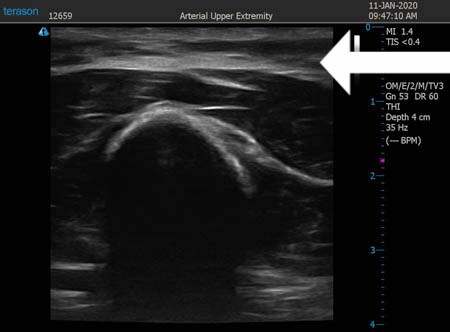

同様に左二の腕 ↓ ↓ ↓

↓ ↓ ↓

左ちからこぶ